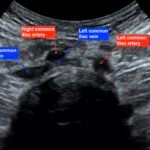

May-Thurner syndrome (MTS) is most commonly caused by the compression of the left iliac vein by the right iliac artery against the lumbar spine, which leads to the development of a partial or occlusive deep venous thrombosis (DVT).1 Diagnosis begins with a duplex ultrasound of the lower extremities to evaluate for a femoropopliteal thrombus, and in high-risk patients where a more proximal DVT is suspected and the DVT ultrasound is negative, a computed tomography venogram (CTV) or magnetic resonance venogram (MRV) is performed.1,3 In this case report, a patient presented to the emergency department (ED) with two days of left lower extremity pain and swelling. Initial lower extremity DVT ultrasound was negative, so a CTV was ordered and revealed a thrombus in the left common iliac vein with overlying compression by the right common iliac artery, suggesting the diagnosis of May-Thurner syndrome (Figure 1). Afterwards, a point-of-care ultrasound (POCUS) was performed at bedside to evaluate the caval and iliac arteries and the findings were consistent with the CTV (Figure 2, 3, 4). If the POCUS was performed prior to the CTV, the patient may have been spared the radiation exposure from CT, as well as the risks of intravenous (IV) contrast required for a venogram. Therefore, in high risk patients in whom a negative DVT ultrasound will prompt advanced imaging with CTV or MRV, I propose the addition of a lower abdominal ultrasound using a curvilinear probe to assess the caval and iliac arteries prior to obtaining a CTV or MRV.